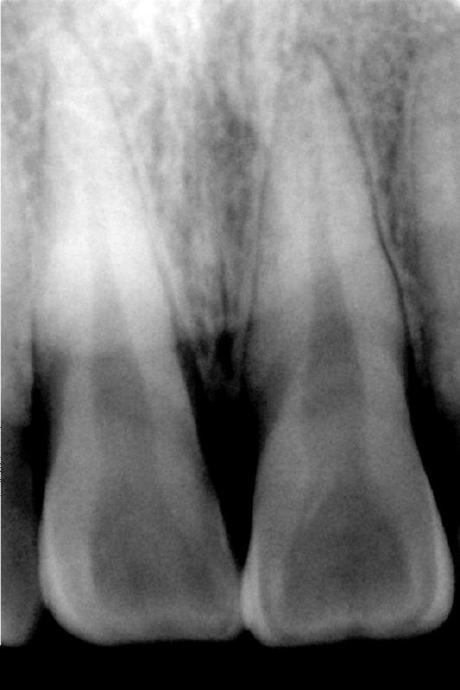

2009年,设计完成了基于英国E2V牙科口内X射线CCD的成像电路设计。设计采用了FPGA(现场可编程门阵列)及高精度ADC,通过高速USB2.0进行高速数据传输。实验结果表明:牙科口内数字成像系统分辨率15lp/mm。该X射线数字成像系统具有体积小、结构简单、分辨率高的特点,能够满足牙齿及指关节等部位实时诊断和工业X射线检测的要求。

本文介绍了一种基于英国E2V牙科口内X射线CCD的成像电路设计,该设计采用FPGA及高精度ADC,并通过USB2.0进行高速数据传输。系统具有体积小、结构简单、分辨率高等特点,适用于牙齿及指关节等部位的实时诊断。